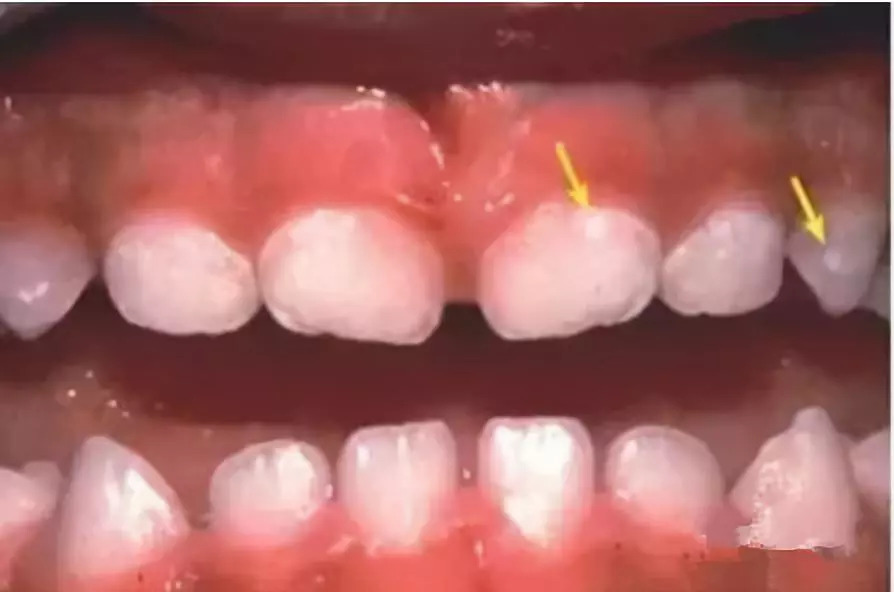

5. 牙面●白斑↓↓

宝宝牙面上出现白斑,这通常是脱矿的表现。建议找专业的牙医进行检查,因为脱矿的牙齿是很容易引起蛀牙的。如果确认脱矿,则需定期给宝宝的牙齿涂氟,同时坚持使用含氟牙膏刷牙。